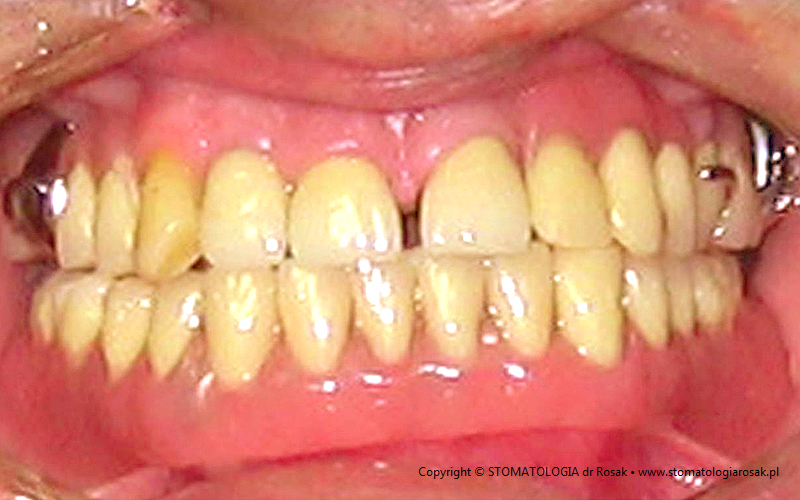

9. Pacjent lat 57- zgłosił się celem usunięcia zniszczonych zębów i wykonania protez ruchomych całkowitych.

NIE USUNĘLIŚMY - ANI JEDNEGO ZĘBA!!!

| 9a. Przed leczeniem |

9b. Gotowe korony i mosty porcelanowe na górze

(trójkę górną prawą pacjent zażyczył sobie nie korygować)

oraz w żuchwie tzw. czapeczki pokrywające oraz zatrzaski kulowe dla lepszego utrzymania protezy ruchomej dolnej |

| 9c. Gotowa praca |